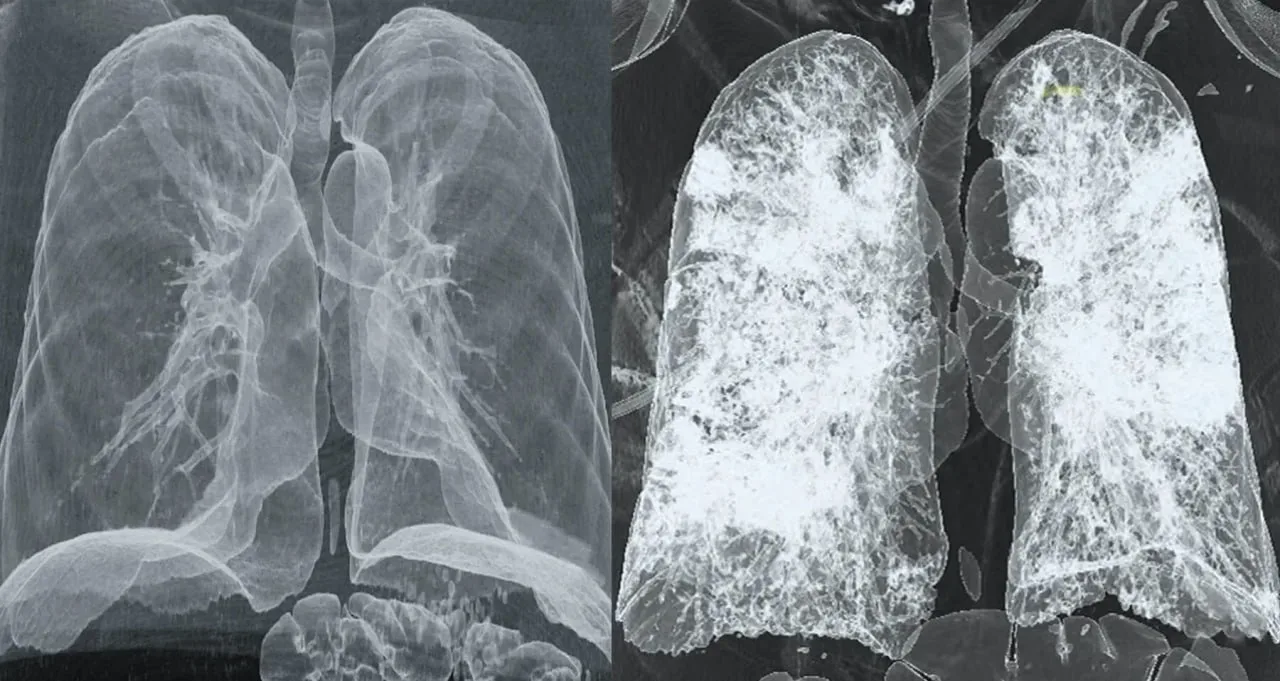

В России зумеры массово попадают в больницы от вейпа Попкорновая болезнь накрывает вейперов России. За последний год число заболевших выросло на 30%. Пульмонологи фиксируют резкий рост тяжёлых заболеваний лёгких среди подростков и молодёжи до 35 лет, которые на регулярной основе курят электронные сигареты. Всё дело в веществе 2,3-бутандионе. Раньше это вещество добавляли только в вейпы с ТГК, чтобы создавать определённый вкус попкорна, но недавно русские производители жижи стали добавлять это вещество во все фруктовые вкусы для создания яркости. Изменения лёгких при вдыхании фатальны. Сначала…